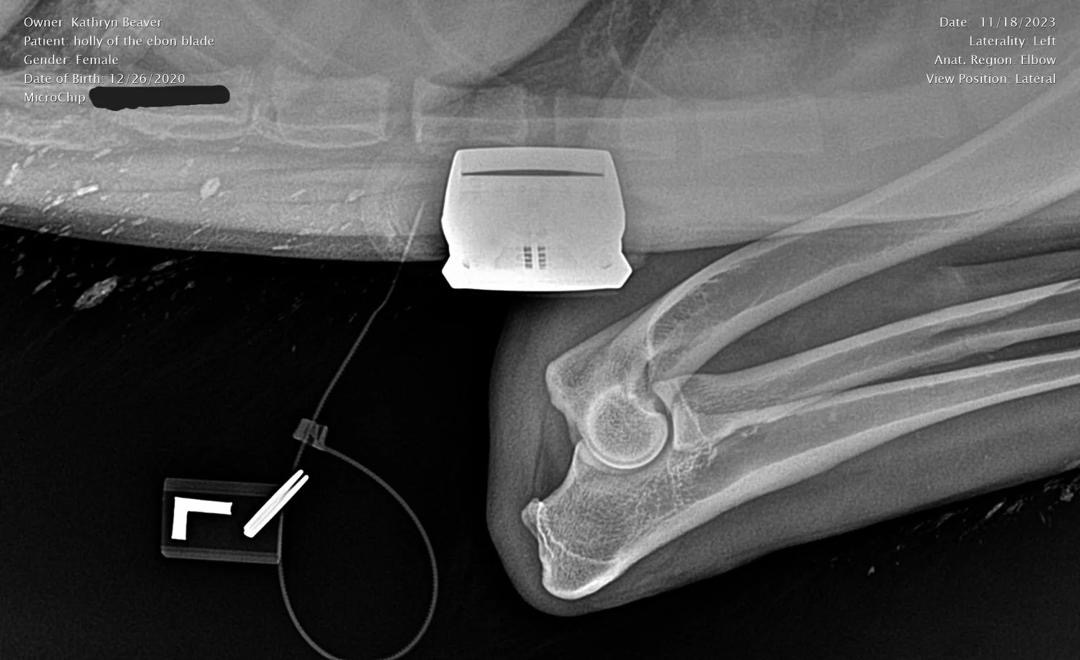

Holly Left Elbow X-Ray

Left Elbow X-Ray

OFA Elbow Evaluation: Normal